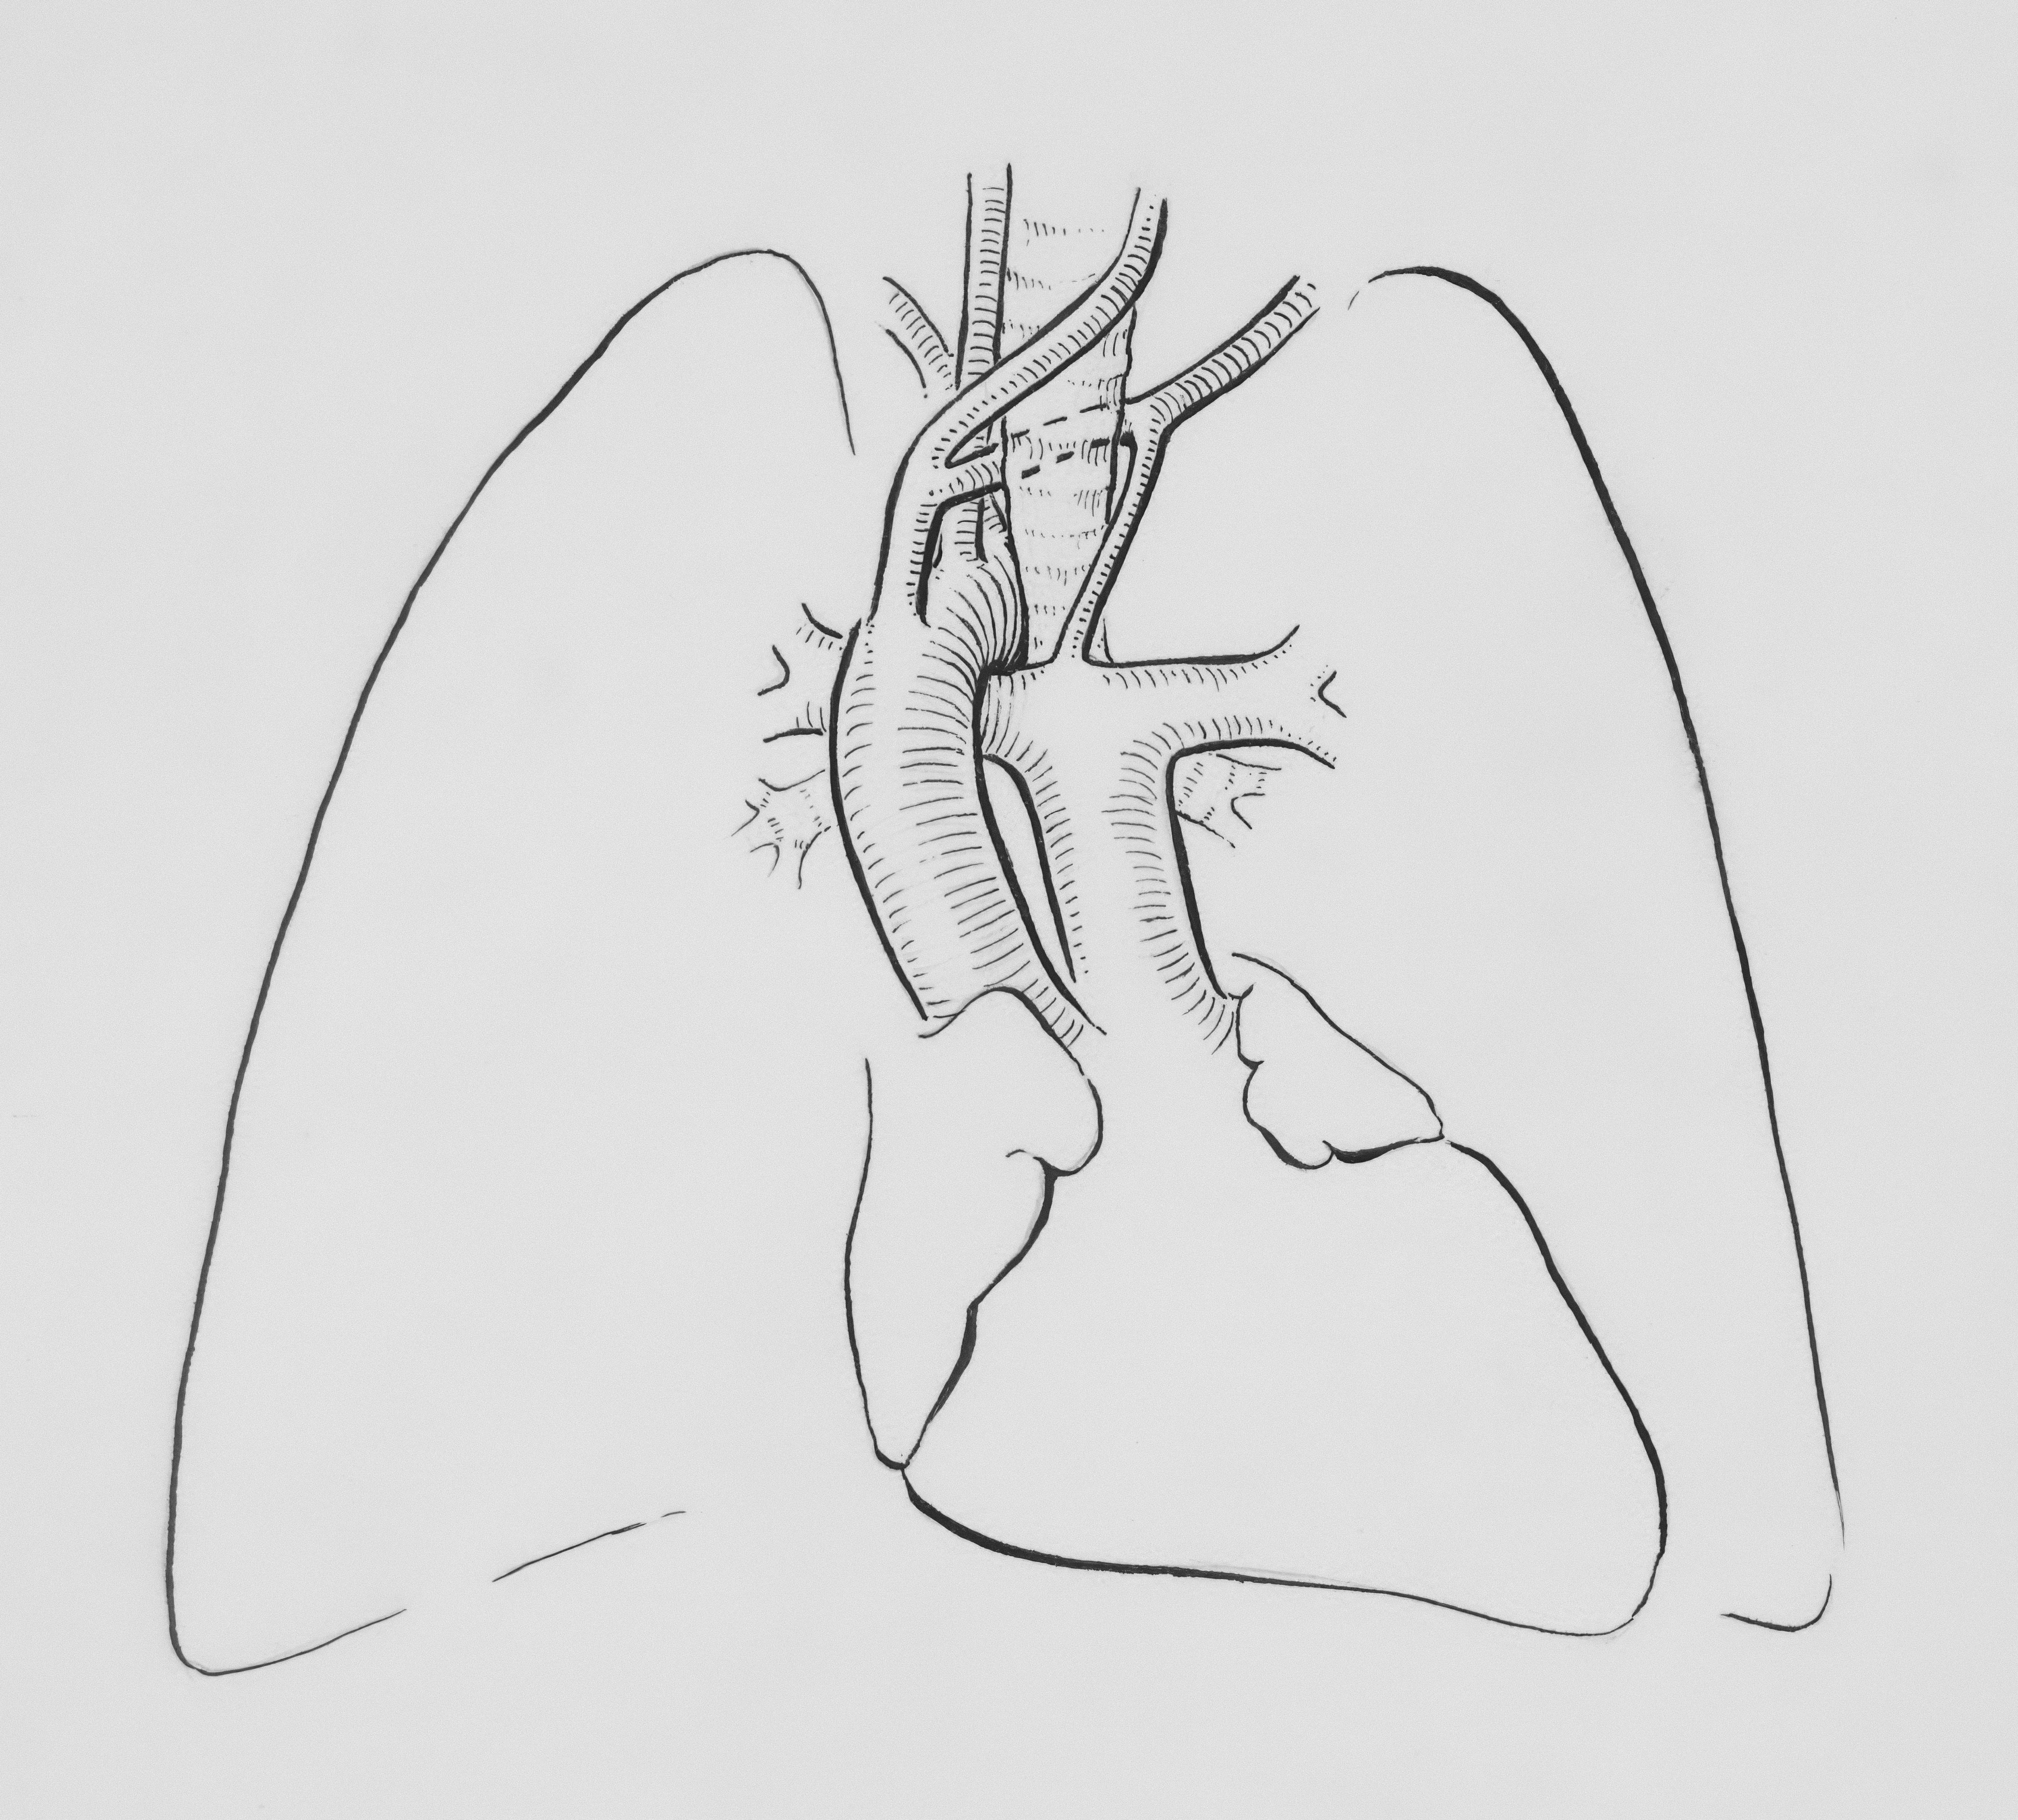

제가 실제로 경험한 지인은 평소 건강한 편이었지만, 심한 감기 이후 호흡곤란을 호소하면서 병원을 찾게 되었어요. 의사 선생님의 설명으로는 폐에 물이 차는 상태는 ‘흉막강’이라는 폐를 둘러싼 공간에 액체가 고이는 현상이라고 했습니다. 이 상태는 단순히 감기 후유증이 아니라, 심부전, 폐렴, 암, 간경변, 신부전 등 다양한 원인에 의해 발생할 수 있다고 해요.

대표적인 치료는 흉수 배액입니다. 보통은 흉강에 관을 삽입하여 액체를 뽑아내는 방식으로 진행됩니다. 이를 ‘흉강 천자’ 또는 ‘흉수 배액술’이라고 하죠.